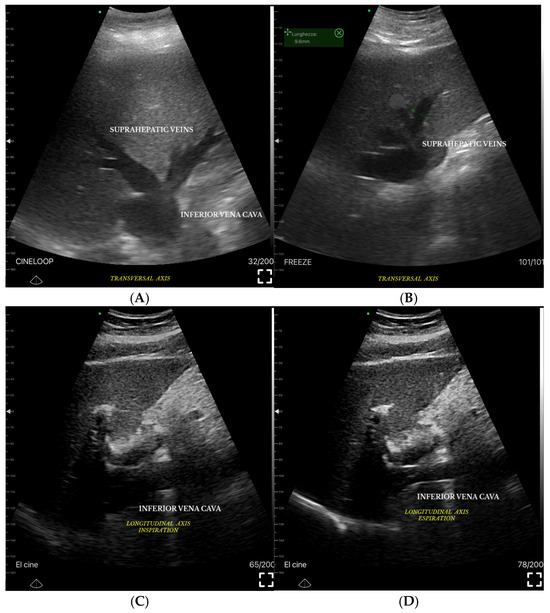

Assessing Venous Congestion in Acute and Chronic Heart Failure: A Review of Splanchnic, Cardiac and Pulmonary Ultrasound: Part 1: Conventional B-Mode, Colordoppler, and Vexus Protocol

Background/Objectives: Heart failure (HF) causes systemic and regional haemodynamic alterations that extend beyond the heart, profoundly affecting splanchnic circulation. Venous congestion is a hallmark of heart failure (HF) and a major determinant of clinical deterioration and multiorgan dysfunction. The splanchnic venous system—comprising [...] Read more.

Background/Objectives: Heart failure (HF) causes systemic and regional haemodynamic alterations that extend beyond the heart, profoundly affecting splanchnic circulation. Venous congestion is a hallmark of heart failure (HF) and a major determinant of clinical deterioration and multiorgan dysfunction. The splanchnic venous system—comprising the portal, hepatic, and renal veins—acts as a key reservoir for intravascular volume redistribution. Conventional ultrasound (US), using grayscale and Doppler imaging, offers a direct, non-invasive approach to visualize these haemodynamic changes. This review, Part 1 of a two-part series, summarizes the current evidence and clinical applications of conventional US for assessing splanchnic, cardiac and pulmonary vascular alterations in patients with HF. Methods: A systematic review was performed in PubMed, Embase, and the Cochrane Library up to current date, following PRISMA 2020 guidelines. Eligible studies included adult human investigations evaluating splanchnic vascular changes in HF using B-mode, color Doppler, or pulsed Doppler ultrasonography. Exclusion criteria were pediatric, animal, or non-English studies and non-standard imaging methods. Data on ultrasonographic parameters, haemodynamic correlations, and prognostic value were extracted and qualitatively synthesized; Results: A total of 148 eligible studies (n ≈ 7000 patients) demonstrated consistent associations between HF severity and alterations in splanchnic, cardiac and pulmonary flow. Findings included increased bowel wall thickness, portal vein dilation with elevated pulsatility, and monophasic or reversed hepatic vein waveforms, all correlating with higher right atrial pressure and adverse clinical outcomes. The integration of these parameters into the Venous Excess Ultrasound (VExUS) framework enhanced detection of systemic venous congestion, in addition to the study of the cardiac and pulmonary circulation. Conclusions: Conventional ultrasound assessment of splanchnic vasculature provides valuable, reproducible insight into systemic congestion in HF. Incorporating hepatic and portal Doppler indices into standard evaluation protocols may improve risk stratification, optimize decongestion therapy, and guide management. Further prospective randomized and outcome-driven studies are required before VExUS-based therapeutic thresholds can be universally recommended and define prognostic thresholds. Full article